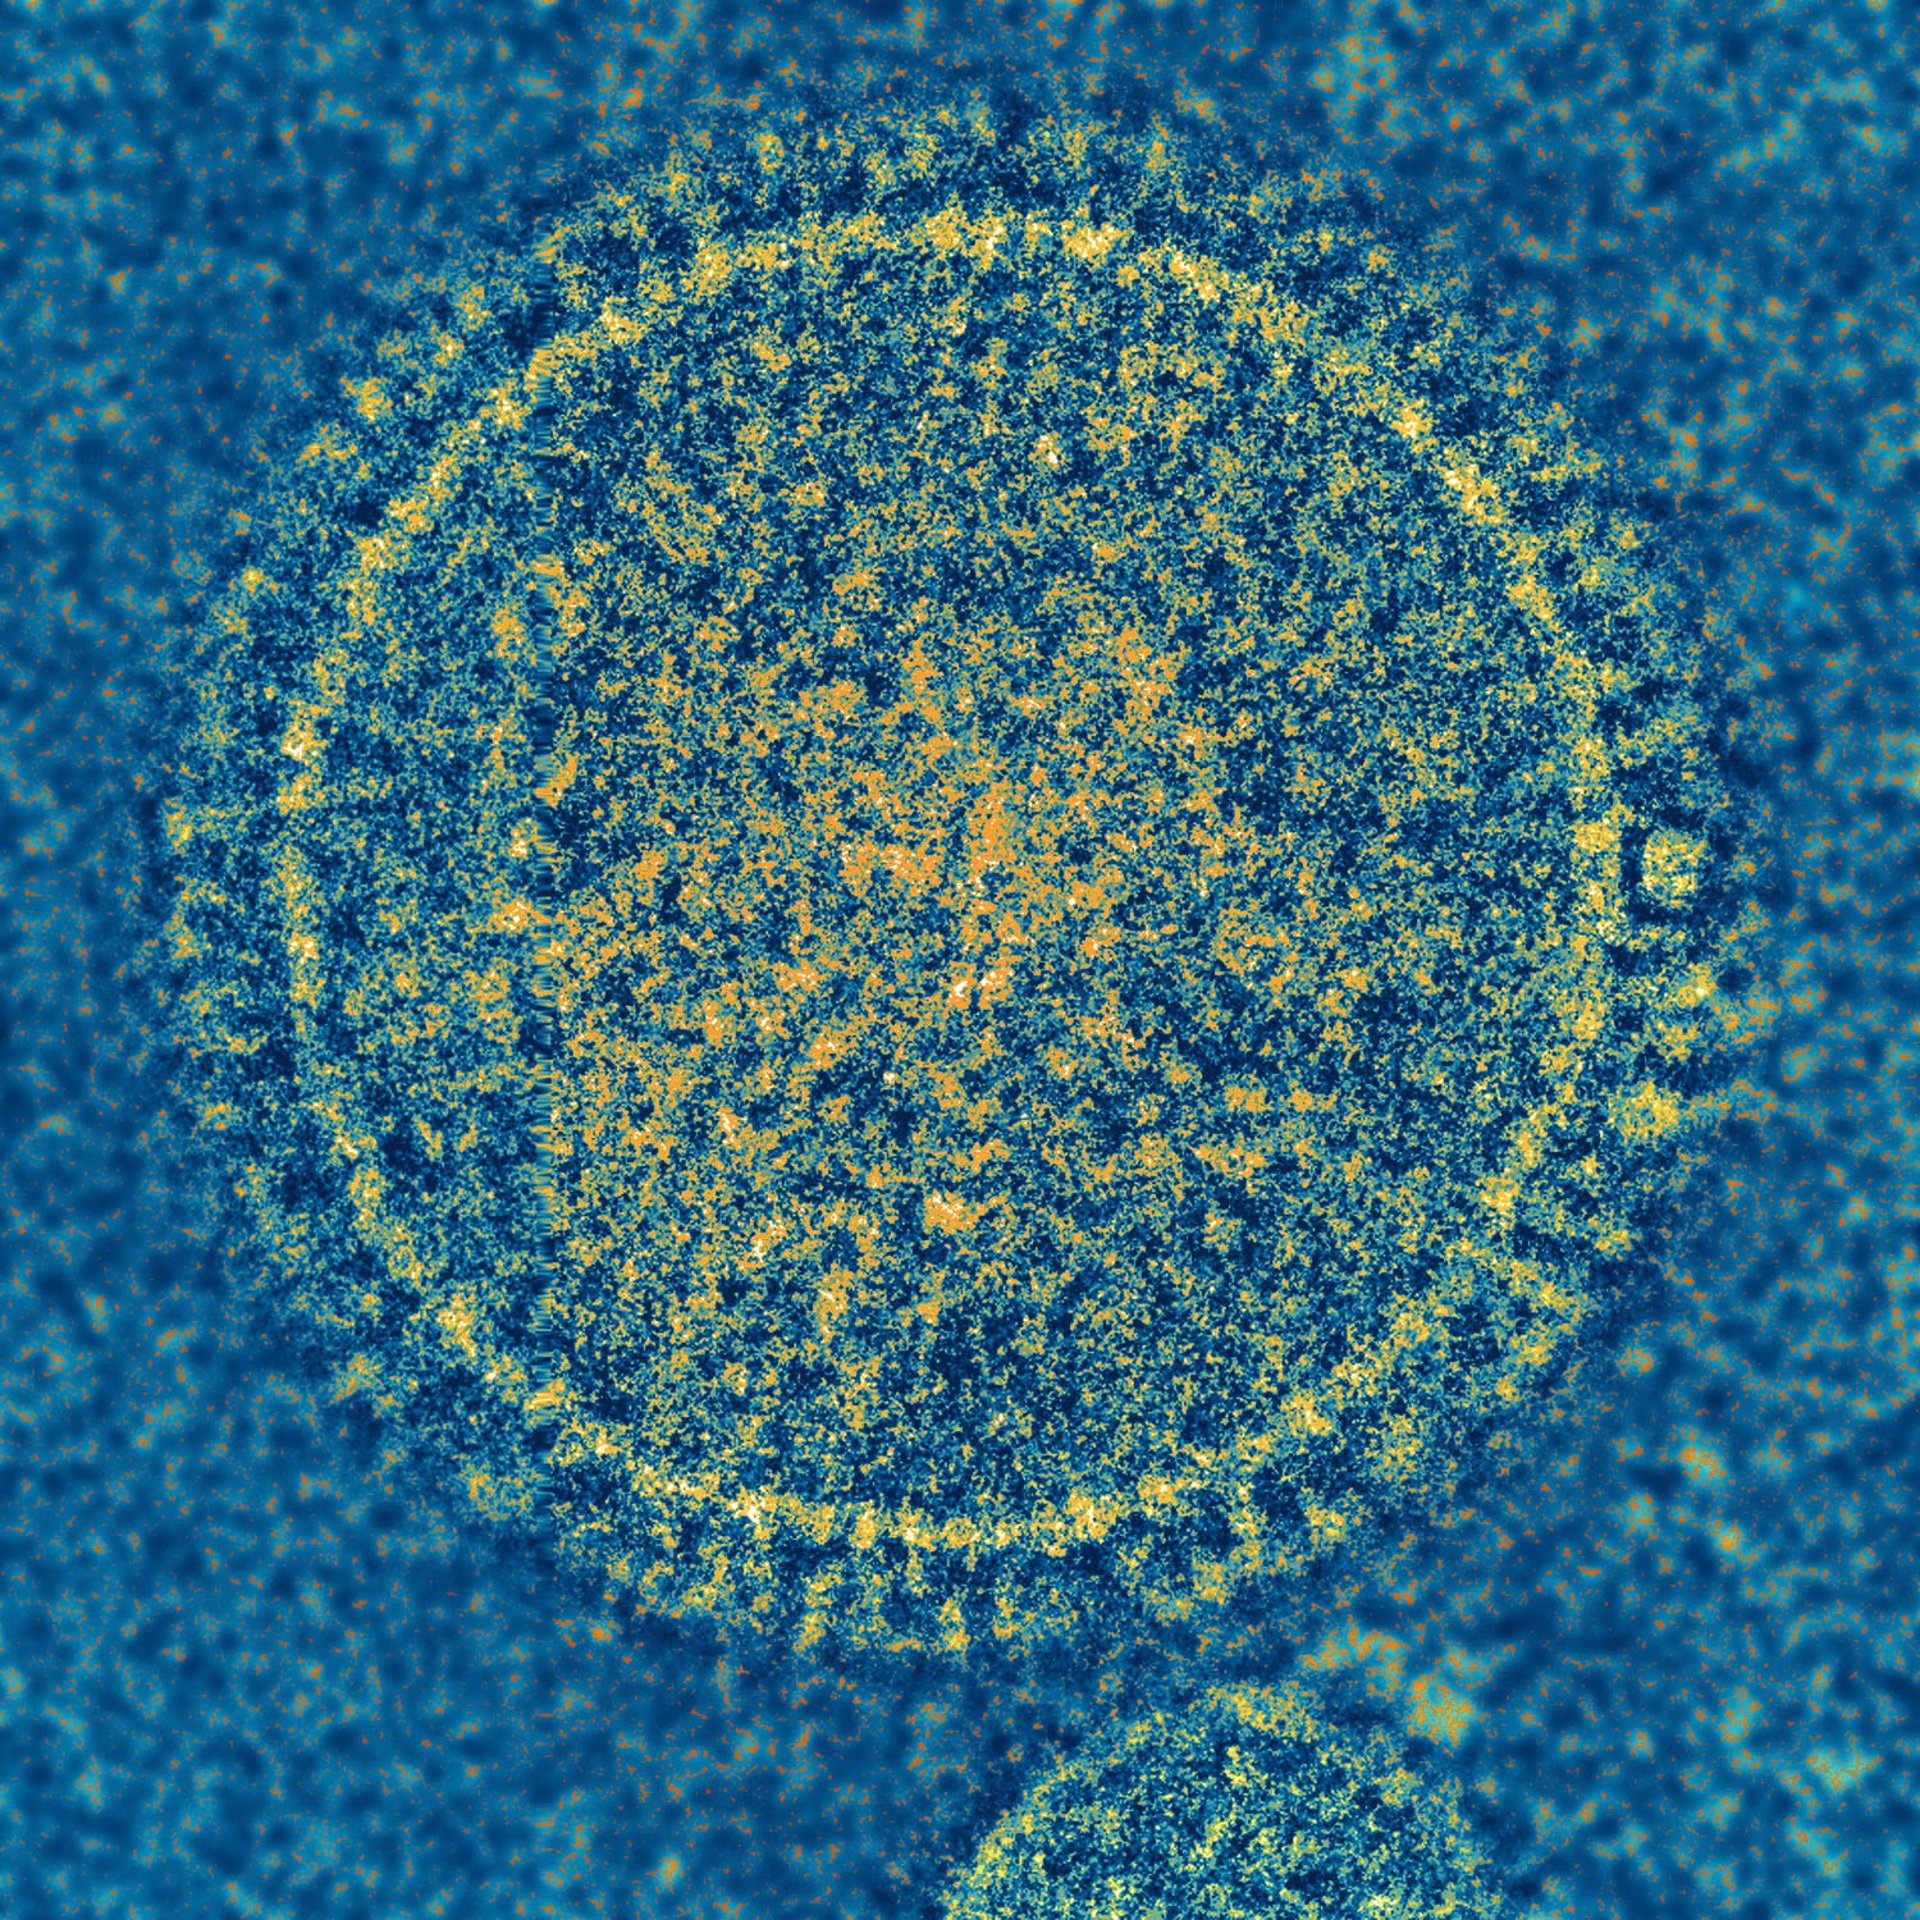

Expertos estiman que el 20% de los menores de dos años que han tenido VRS sufrir - NIAID - Archivo